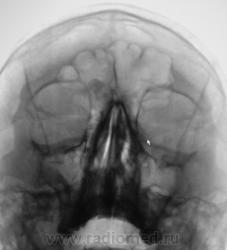

Касательно пристеночного уплотнения справа в в/ч пазухе- вполне возможно суммационное искажение из-за неправильной укладки,с учетом клиники-я бы перестраховался и назначил томограмму(в идеале-малодозовый режим СКТ на ППН). Можно назначить контроль в динамике.

что-то плотное в правой лобной пазухе- остеома?

Образование правой лобной пазухи,пристеночное утолщение слизистой пр.гайморовой пазухи. Как всегда может помочь томограмма.

Остеома с типичной локализацией. Неосложненная.